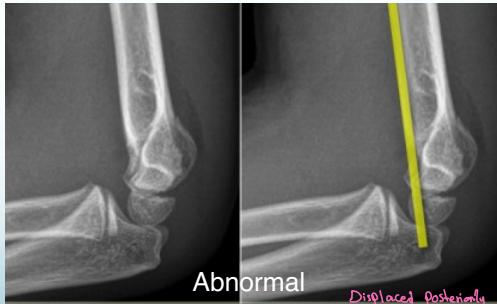

Anterior Humeral Line:

- A line drawn on a lateral view along the anterior surface of the humerus should pass through the middle third of the capitellum

Normal

Abnormal - Displaced posteriorly